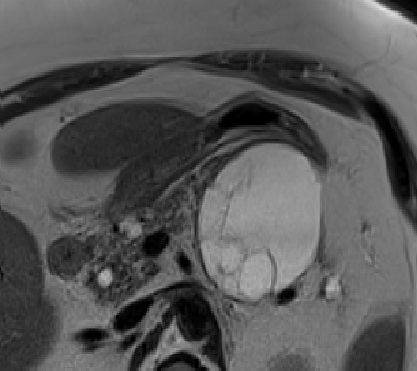

We notice an increasing frequency in the detection and evaluation of pancreatic cystic lesions (PCLs) over the last three decades. They show awide spectrum of imaging and clinical features. The diagnosis and discrimination of these lesions are very important because of the risk for concurrent or later development of malignancy. The main reason is the increased awareness of these lesions and the extensive use of cross-sectional imaging, an always improving technique (1). Commonly, PCLs are diagnosed incidentally during investigation for often unrelated and nonspecific abdominal complaints using state-of-the art abdominal imaging (CT, MRT). The term PCN denotes a histologically heterogeneous collection of neoplasms showing a wide spectrum of diagnoses, ranging from completely benign to potentially malignant, to carcinoma in situ, to frankly invasive and malignant (2,3). In 1978, Compagno and Oertel were the first to recognize the crucial distinction between the serous and the mucinous cystic neoplasms of the pancreas by explaining the importance of identifying the mucinous neoplasms because of their overt or latent malignant potential (4,5). Since then, the interest in PCLs increased markedly, especially so with the recognition of the importance and prevalence of intraductal papillary mucinous neoplasms (IPMNs). Nowadays, PCLs represent a common and often difficult challenge in clinical practice, because of the increase in their detection in asymptomatic patients and our still immature understanding of some aspects of their biologic behavior. Their important differences regarding their outcome and the fact of being increasingly often identified has put a special focus on these neoplasms by surgeons, pathologists, gastroenterologists, radiologists, and oncologists alike. Management of patients with PCNs can be challenging and varies considerably among the various subtypes of PCNs. Their treatment ranges from resection of malignant lesions, to resection and/or surveillance in the case of premalignant lesions, to simple observation in the case of benign or indolent lesions. Under these circumstances, the accurate classification of PCNs becomes crucial. Therapeutic decision making and classification rely mainly on the presenting symptoms and radiologic findings, often without actual histologic tissue. It is of extreme importance to identify suspicious features indicating potential or certain malignancy in order to select the appropriate treatment. The risk of overtreatment (unnecessary pancreatectomy) should he balanced carefully with the risk of under treatment (missing the opportunity to cure a potentially curable malignant or premalignant disease).